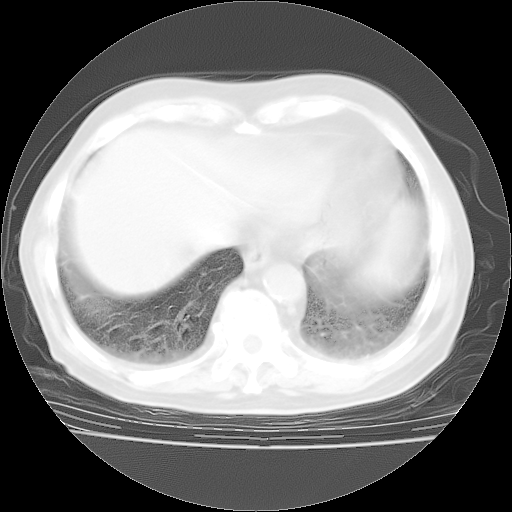

4月28日肺部CT——再次出现类似去年5月9日——磨玻璃样、间有“粟粒样”改变。

个人阅读4.14日肺部CT平扫:纵隔窗无异常,但肺窗示:双下肺内、后基底段有片絮状侵润影,部位以后基底段为著,以间质改变为主,呈急性肺泡炎征像,和首次住院影像学有相似之处。仅是个人读片,明日请相关专家再读片哈。其它建议同上。